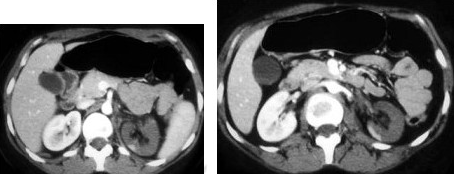

36、单项选择题

男,60岁,曾患乙肝、肝硬化多年,右上腹胀痛1月余,AFP为80.8μg/L,CT检查如图所示,最可能的诊断是()

A.肝硬化结节增生、右肾上腺瘤

B.肝、右肾上腺均为转移癌

C.肝癌右肾上腺转移

D.肝腺瘤、右肾上腺腺瘤

E.肾上腺癌肝转移